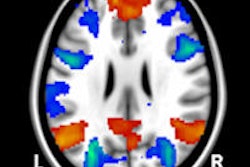

The latest thinking on resting state functional MRI (rsfMRI) came under scrutiny during Friday's hot topic debate. Although rsfMRI shows great potential, opinion is divided about whether these examinations will ever be useful in clinical practice. Get the story here.

Research into rsfMRI also accounted for two of the top prizes given to electronic poster exibits during the ESMRMB congress. The prize-winning studies were conducted in London and Grenoble, France. Click here to read more.